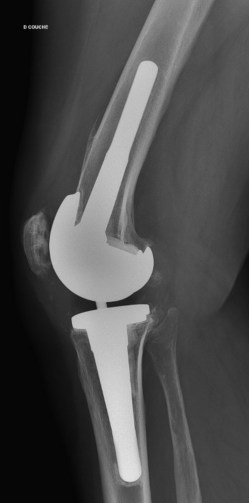

J’ai passé mon dimanche à chercher un orthopédiste à Montpellier, au CHU de Lapeyronie, n’en connaissant pas difficile d’en choisir un bon. Ce fut donc au hasard et pour une fois j’ai eu de la chance. En effet le lundi matin la secrétaire m’a dit qu’i y avait un désistement le lendemain matin à 8h30. Le Dr m’a refait passer des radios sur place et le résultat est le même : Prothèse et rotule sont bien en place. Je ne sais toujours pas ce que j’ai donc ! Du coup je passe un scanner ce jeudi 2 juin 2022 et vais revoir le Dr le 7 juin.